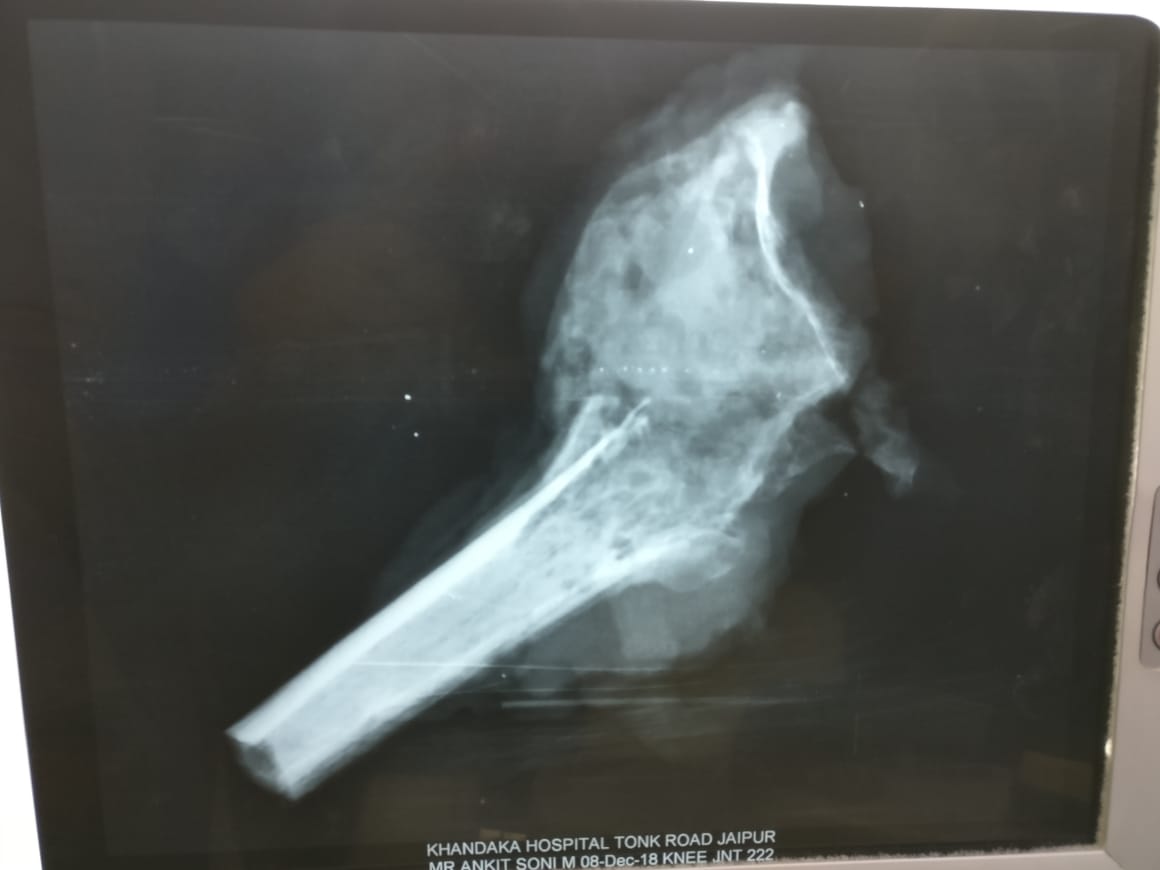

Translocation of Ulna for GCT Of Distal Radius